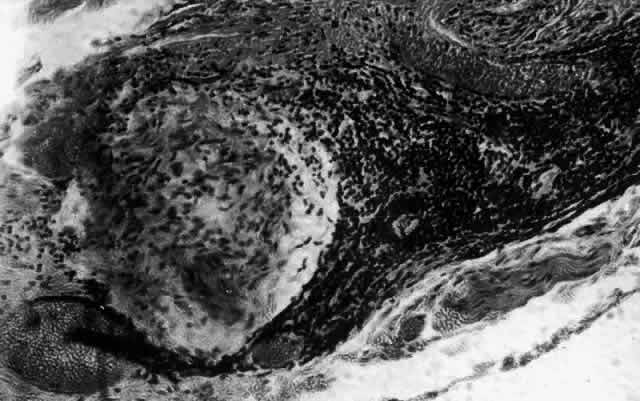

What is clinically represented solely by inflammation and edema is histopathologically a granulomatous lesion of the sclera, the center of which consists largely of plasma cells, lymphocytes, and mast cells (Figs. 21 through 23). Foster and colleagues have identified the cellular subsets and glycoproteins in both necrotizing and non-necrotizing scleritis.22 This shows an active T-cell inflammatory response with a high CD4/CD8 ratio and increased HLA/DR and CD14, indicating a macrophage-induced response that would lead to granuloma formation. Remote from the granuloma, the fibrocytes of the sclera become activated, the proteoglycan adjacent to them becomes altered, and the collagen fibrils of the sclera become unraveled (Figs. 23 and 24). These changes appear to take place prior to the invasion of the stroma by cells of the granuloma.20 The vessels in and around the necrotic area show medial necrosis and perivascular cuffing with lymphocytes, and endothelial swelling with microvascular occlusion. Ninety-six percent of the specimens examined by Foster and associates show a microangiopathy characterized by a neutrophil infiltrate in and around the vessel wall.22–23 This is most obvious at the center of the lesion where there may be occlusion of the vessel, thrombosis, or even aneurysm formation (Fig. 25). From these pathologic investigations, clinical observations, animal experiments, and the results of fluorescein angiography, it would appear that the scleral inflammation is initiated either by trauma (be it accidental or surgical)23–25 or by bacterial or viral infection. If circulating immune complexes are present because of the poor blood flow, they become precipitated in and around the vessel walls in the area of inflammation. In other patients, a persistence of tissue damage will lead to autoimmunization. Damage to the endothelial cells of the microvasculature leads to changes within the vessels detectable on angiography and to catabolic changes in the surrounding tissues. These changes, in turn, allow the granulomatous response that is seen in histopathologic sections, the first detectable change being in the scleral fibrocytes and the proteoglycan and collagen remote from the site of cellular infiltration.

Fig. 21. Advancing edge of a granulomatous reaction. Scleral fibers are split and separated by edema and then disrupted when invaded by the granuloma

Fig. 22. Electron micrograph of an area of active scleritis showing the plasma cell infiltrate suggestive of an immune response. Note aggregated plasma cells, with the characteristic whorled rough endoplasmic reticulum, in the process of degeneration, releasing organelles and nuclear debris into the extracellular matrix. (Uranyl acetate and lead citrate. X3000) (Courtesy of Dr. R. Tripathi)

Fig. 23. Electron micrographs of scleral stroma at the periphery of an area of ulceration in a patient with necrotizing scleritis. The left shows an active fibroblastic cell, and the right shows collagen fibrils within intracellular vacuoles (V) in the fibroblastic cell. (Left X15,375; right X15,375) (Watson PG, Young RD: Changes at the periphery of a lesion necrotizing scleritis: Anterior segment fluorescein angiography correlated with electron microscopy. Br J Ophthalmol 68:781–789, 1984)